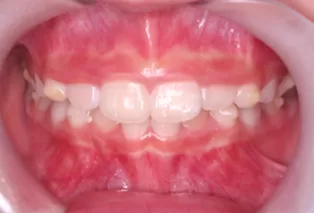

Photos intra-orales